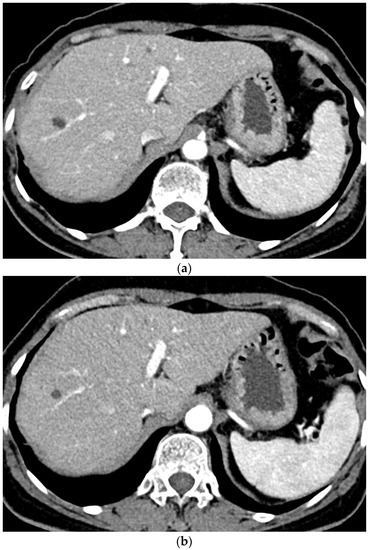

In each group, some quantitative parameters were significantly different between the machines that performed CT examinations (Figure 2). In Group A, the SNR of all the organs and the CNR of all the organs except the liver were significantly higher with machine B than machine A. In Group B, the SNR of the pancreas, spleen, and kidney and the CNR of the pancreas, spleen, and portal vein were significantly higher with machine B than machine A. The machine A frequently selected tube voltage 100 kVp or higher than machine B with statistical significance (Group A: 93.6% vs. 47.4%, p < 0.001; Group B: 83.3% vs. 40.2%, p < 0.001). All quantitative analysis parameters were significantly higher in CT scans with lower tube voltage than those with higher tube voltage in both groups (Table 5).

Figure 2. Differences in the signal-to-noise ratio (SNR) and contrast-to-noise ratio (CNR) between the two machines in each group SNR and CNR of the organs in Group A (a,b) and Group B (c,d), respectively. * p < 0.05; ** p < 0.01; *** p < 0.001.